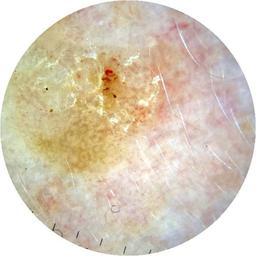

diagnosis_1 Malignant

diagnosis_2 Malignant adnexal epithelial proliferations - Follicular

diagnosis_3 Basal cell carcinoma

image_type dermoscopic